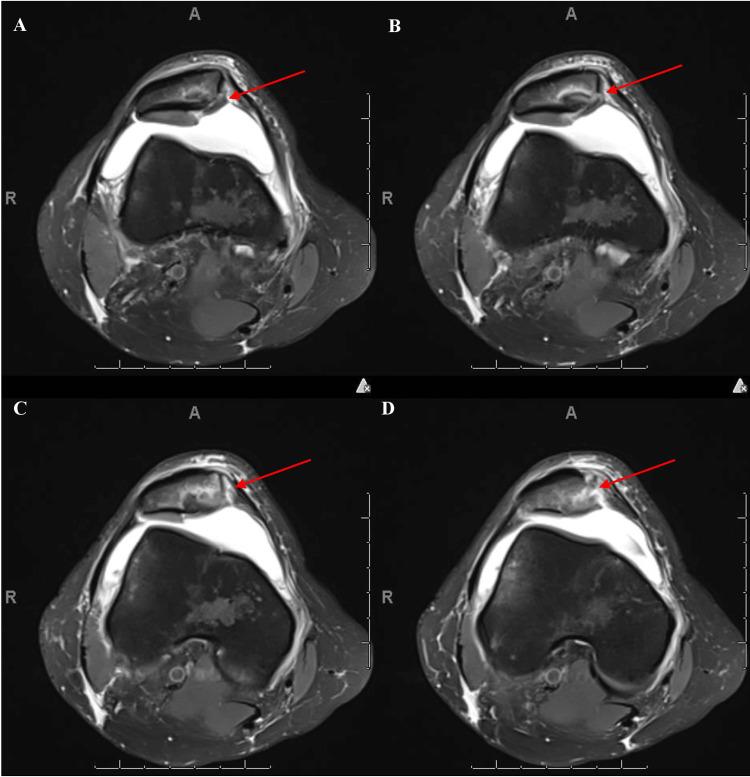

Patellar dislocation most commonly occurs laterally and is associated with underlying anatomical abnormalities such as trochlear dysplasia and patella alta. While osteochondral injuries typically involve the lateral femoral condyle, simultaneous osteochondral fractures of the medial patella and lateral femoral condyle are extremely rare and often under-diagnosed due to subtle imaging findings and spontaneous patellar reduction. The purpose of this report is to highlight a rare injury pattern following lateral patellar dislocation and to emphasize the importance of early diagnosis using advanced imaging to prevent long-term complications. This retrospective case report describes a 22-year-old female patient who presented two weeks after a lateral patellar dislocation with knee pain and limited range of motion. Diagnostic imaging, including CT and MRI, was used to evaluate the extent of injury. The patient underwent surgical intervention consisting of arthroscopic and open fixation of osteochondral fragments using K-wires and ConMed smart nails, along with retinacular release. Postoperative outcomes were monitored over an eight-month period to assess recovery, range of motion, and symptom resolution. Intraoperatively, a large osteochondral fragment was found embedded in the medial patella, matching a defect in the lateral femoral condyle. Fixation was successful. At one-week follow-up, the patient showed improvement in pain and function. By eight months, she regained full range of motion, ligamentous stability, and resolution of symptoms. Simultaneous osteochondral injury to the medial patella and lateral femoral condyle is a rare but significant complication of lateral patellar dislocation. Prompt diagnosis and surgical fixation lead to favorable outcomes.